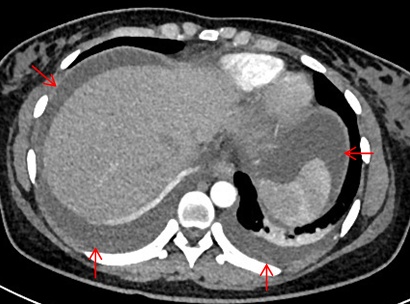

办好住院已经是1月13日下午四点了,介入科方淳主任及团队加班加点,当天晚上就为患者做了肠系膜动脉和静脉造影,结果没有发现大血管的问题,但是小血管充血、丰富,呈梳子样改变(称为“梳子征”,图1)。排除了肠系膜大血管的问题之后,高度怀疑肠系膜小血管炎可能,事不宜迟,赵家胜主任通过电话联系到风湿免疫科值夜班的王璇主治医生,王医生仔细询问了病史,了解到患者有过脱发和自发性流产的病史,结合本次肠道小血管炎的表现,高度怀疑系统性红斑狼疮引起的肠系膜血管炎。为了缓解患者的腹痛,挽救病人的生命,王璇医生基于对病情的判断,在化验结果尚未出来的情况下果断使用了糖皮质激素,第二天早上(1月14日)患者腹痛和恶心、呕吐即明显好转,患者胃口也开了,随后吃了点半流质,但下午又出现了腹痛和呕吐,这时化验结果也出来了(见图2),狼疮的标志性抗体-抗Sm抗体和ds-DNA抗体均阳性,证实了系统性红斑狼疮的诊断。赵主任和风湿免疫科汤建平主任共同查房后认为系统性红斑狼疮诊断明确,以急性腹痛起病,而且一发病就表现为狼疮危象的红斑狼疮少见,常规剂量激素疗效不佳,腹部CT结果显示肠壁水肿和胸腹水有进展(见图3、图4),需要立即进行大剂量激素冲击治疗。

图4. 治疗前胸腹水(箭头所示)